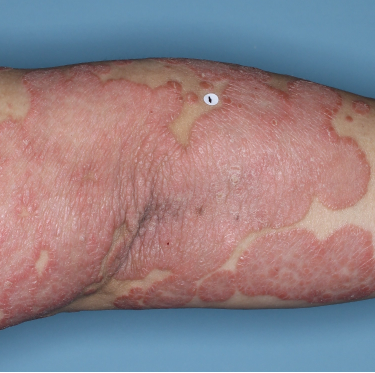

Patients saw clearer skin at Week 16 and Week 481,2

Week 0

PASI=20.6

Week 16

PASI=2.9

(86% PASI

improvement)

Week 48

PASI=1.10

(95% PASI

improvement)

Individual results may vary.

Images are Janssen-owned from blinded trial: NCT05272150.